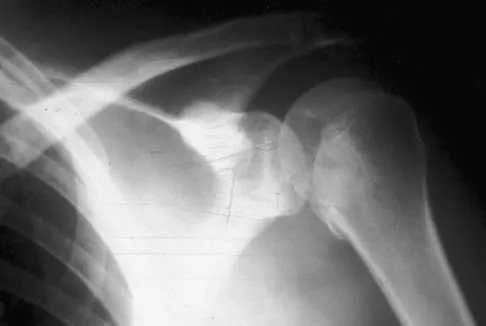

A 40-year-old woman who is an avid tennis player reports the insidious onset of progressive left shoulder pain for the past 2 months. Examination reveals full range of motion with a positive impingement sign. Strength in the supraspinatus and infraspinatus muscles is normal, although stress testing is painful. An earlier subacromial cortisone injection provided good, but only temporary relief. An AP radiograph of the left shoulder is shown in Figure 10. Management should now consist of

Explanation

The radiograph shows calcific deposits within the substance of the supraspinatus tendon. Patients with this condition are prone to recurrent bouts of acute inflammation in the shoulder. While the response to cortisone injection is often dramatic, repeated injections are not recommended because of injury to the collagen fibers. Good results have been obtained with arthroscopic evacuation of the calcium deposits. In one study, the addition of a subacromial decompression did not improve the results. Jerosch J, Strauss JM, Schmiel S: Arthroscopic treatment of calcific tendinitis of the shoulder. J Shoulder Elbow Surg 1998;7:30-37.